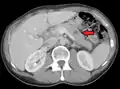

صورة أشعة مقطعية لانبثاثات متعددة بالكبد